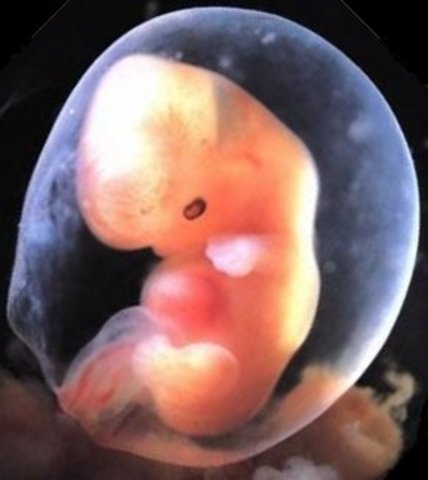

• Week 7 of the First Trimester

Week 7 of the First Trimester

The Embryo will begin to develop its major organs and its heart will start to beat.

Facts:

1)The embryo is around 13 mm (1/2 inch) in length.

2)The baby's eyes and inner ears are starting to develop.